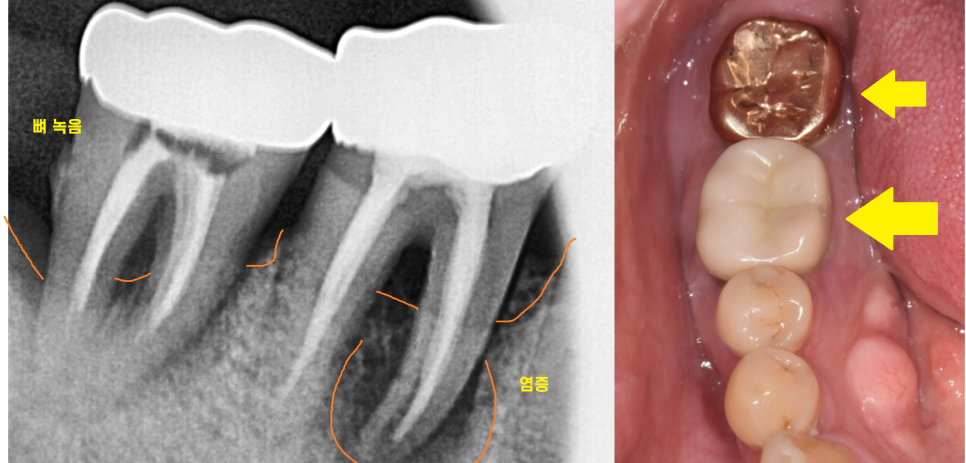

겉으로는 멀쩡해보여도

엑스레이를 찍어보면 치아 뿌리 주변 염증이 있는 것을 확인할수가 있네요~